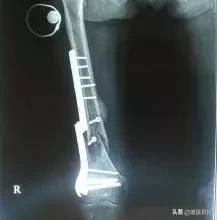

对于靠近关节部位的钢板,由于我们对于关节的功能要求很高,存留的异物有时会成为影响关节活动的罪魁祸首。如肩锁关节部位的锁骨钩钢板,脚踝部位的螺钉、手指或者掌骨的克氏针等,如果不取出来都会影响关节活动。在一些身体的特殊部位,比如皮肤菲薄的小腿,爱美女性的锁骨,钢板很容易触及,一方面摸着不舒服,另一方面钢板与皮肤反复摩擦容易损伤娇嫩的皮肤,甚至还可能造成皮肤破损。这些情况下,可能取出钢板对自己更为有利。

体内深部的钢板

体内深部的钢板,比如骨盆钢板因为太深,取出操作损伤大,很容易造成大出血,取出风险非常高。对于脊柱手术用的钢板螺钉,由于部位的特殊性,钉棒系统不只是治疗骨折,很多脊柱疾病可以通过钉棒或者其他内固定植入物增加脊柱力学的稳定性,矫正畸形等,因此对于脊柱的内固定多数情况下是不需要取出的。